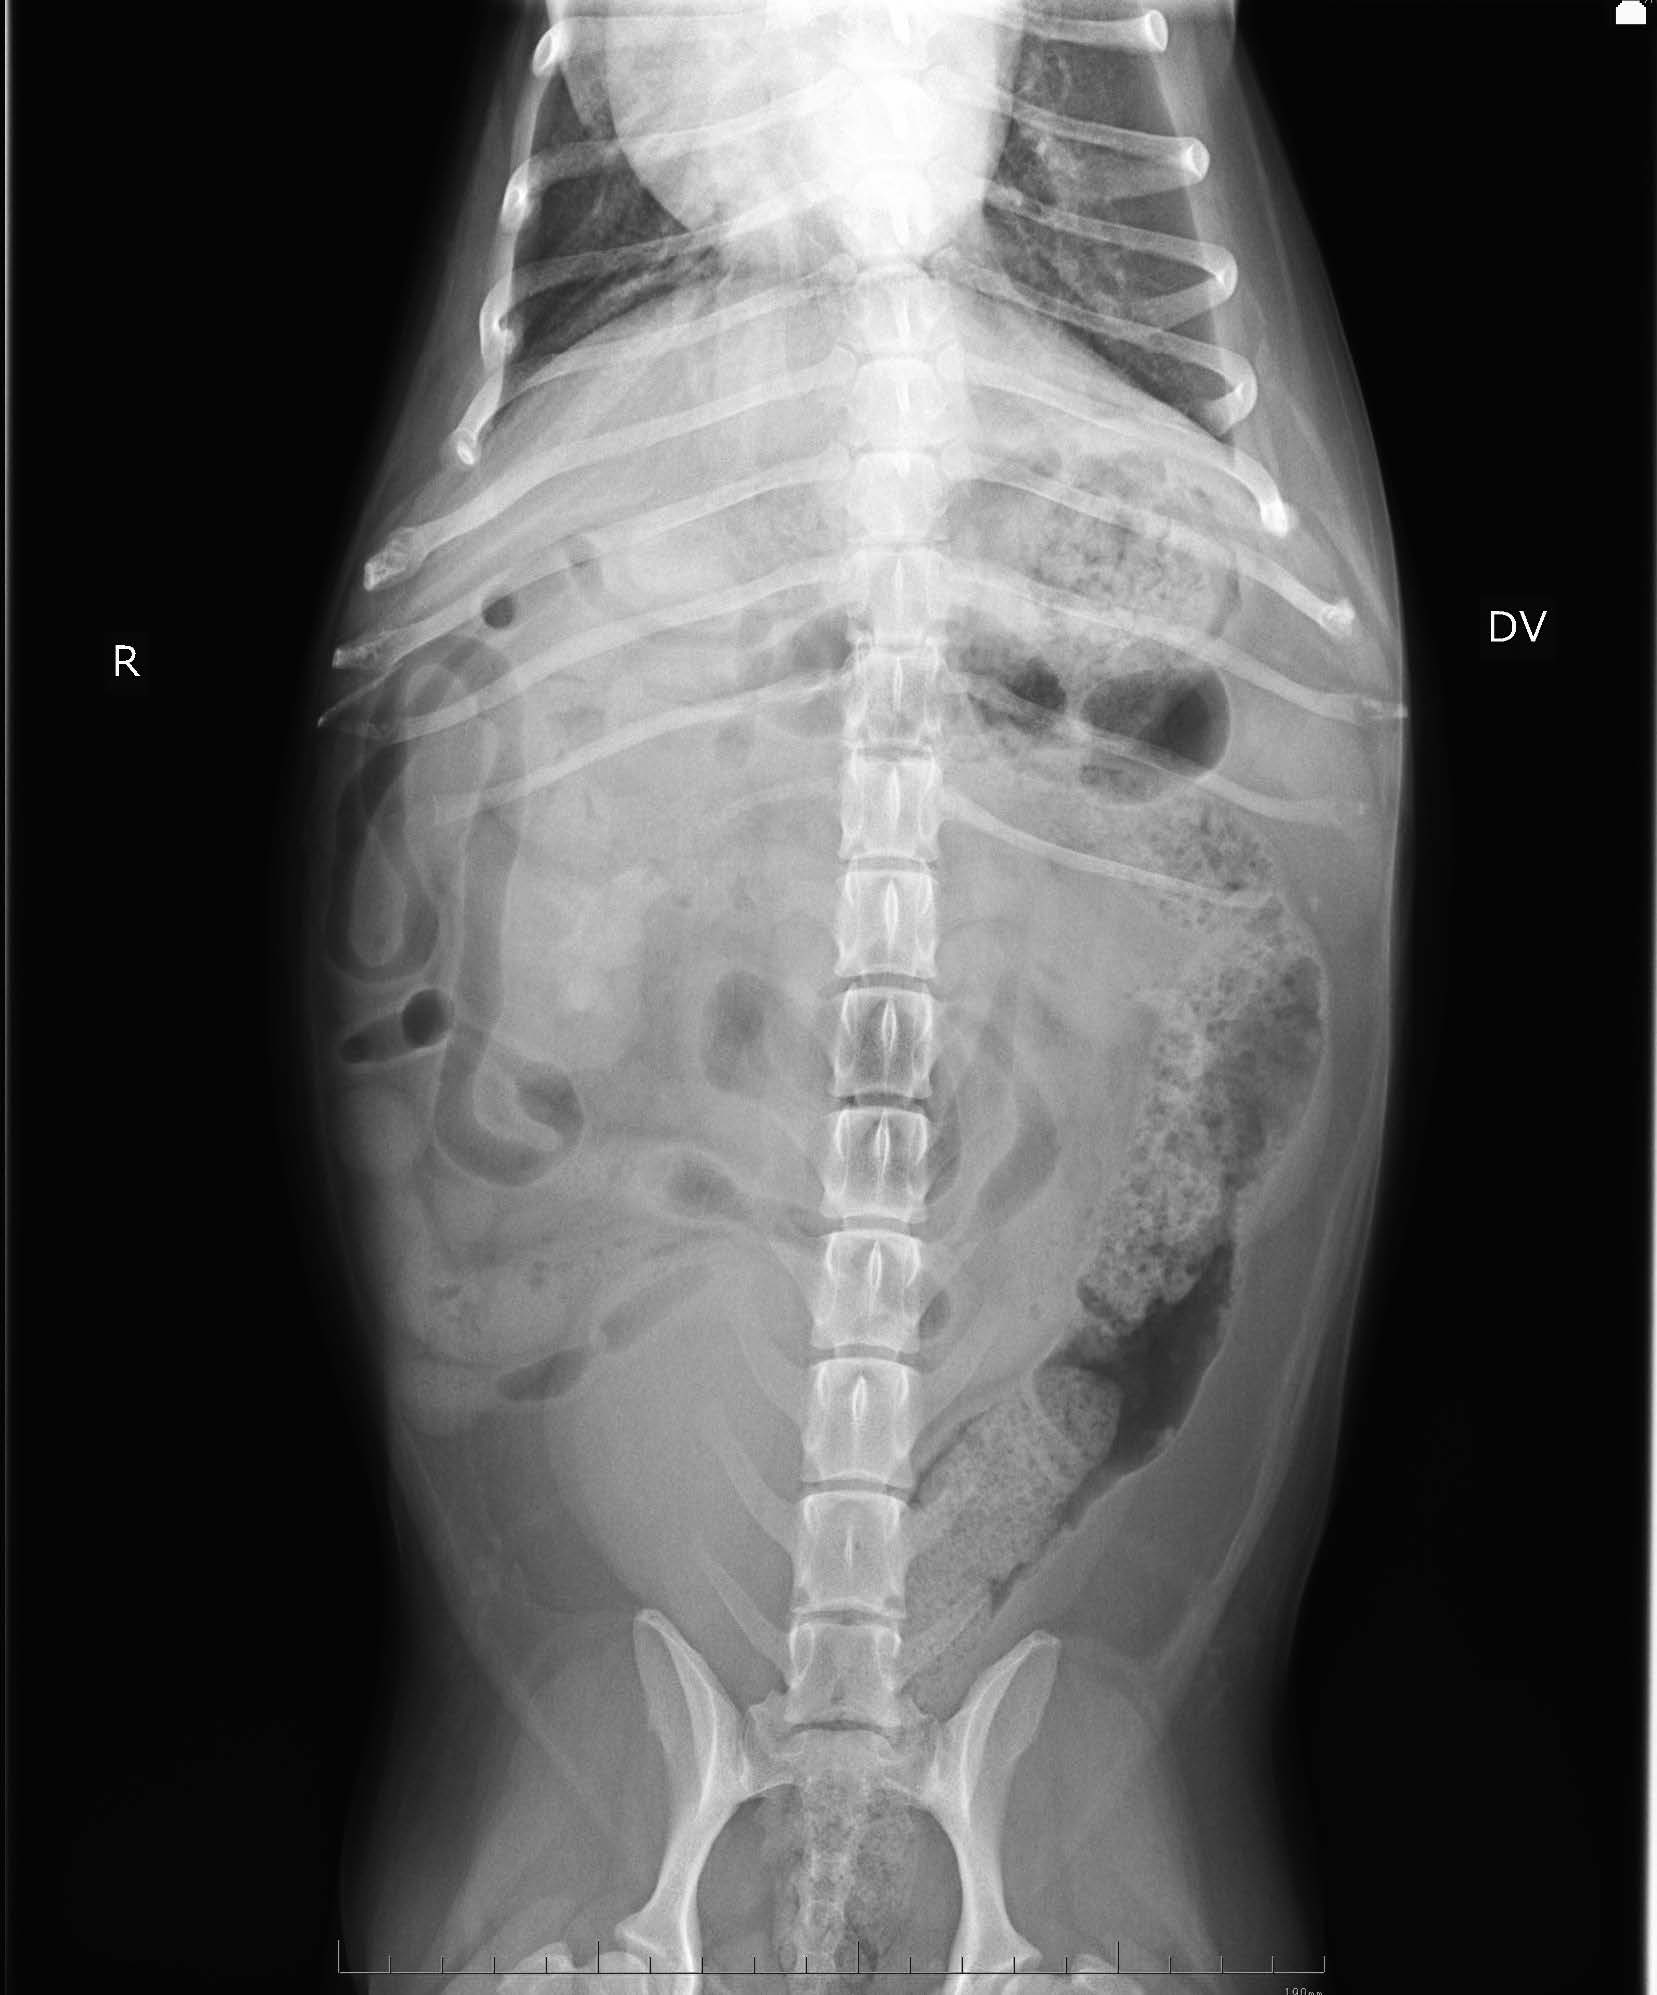

画像検査:腹部X 線検査では,肝サイズの低下と両腎にX 線不透過性の低い陰影が認められた(図1).腹部超音波検査では両側腎盂領域において,音響陰影を呈する高エコー構造物を認めた(図2).膀胱内には,高エコー源性の浮遊物及び沈渣が観察された.

図2 右腎臓の超音波検査画像

腎盂内を占拠する物体の音響陰影を認める.